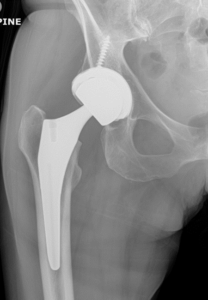

Femoral neck fractures occur when there is a break in the segment of bone that connects the thigh bone to the femoral head (Figure 1a). The femoral head is the “ball” portion of the hip joint which makes up the ball and socket of the joint. When the ball shifts out of place as a result of this fracture in an elderly individual, the treatment is often a form of hip replacement surgery (Figure 1b). When the ball has not shifted significantly, screws are often inserted to fix the bone in place (sometimes referred to as a pinning procedure, Figure 1c).